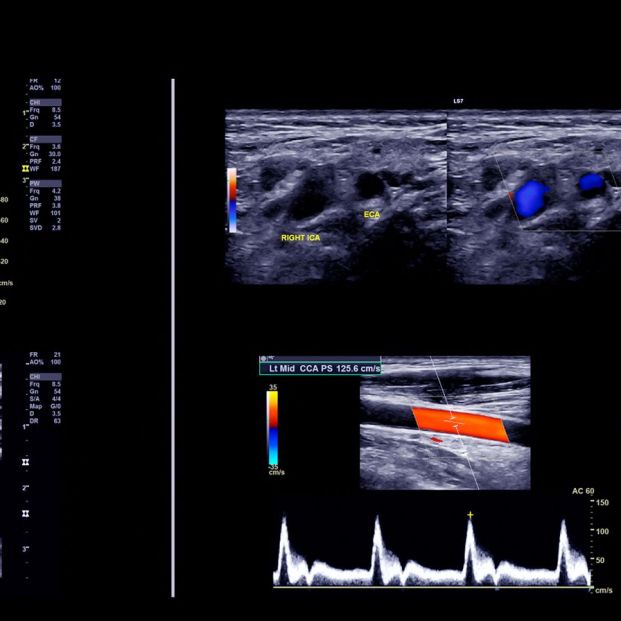

El Doppler actúa a través de un gel conductor que se aplica en la zona que se desea visualizar (igual que cualquier ecografía tradicional), reflejando en el monitor los cambios apreciados. Los dispositivos más avanzados de pulsación discontinua, capaces de asignar distintos colores a los vasos sanguíneos, permiten detectar fácilmente cualquier anomalía que estos puedan presentar, como un estrechamiento o estenosis o situaciones patológicas que impliquen un serio peligro, como puede ser la presencia de un trombo, la inflamación de la vena (felbitis) o un aneurisma.

La técnica de ultrasonido y los resultados visibles que ofrece también permiten conocer si existe algún tipo de reflujo en el torrente sanguíneo, algo de especial importancia a la hora de prevenir cualquier valvulopatía que esté afectando al correcto funcionamiento del corazón o provocando una circulación de retorno deficiente. En la prevención y detección de la Insuficiencia Venosa Crónica, es un paso previo a cualquier tratamiento que corrija o frene esta enfermedad.